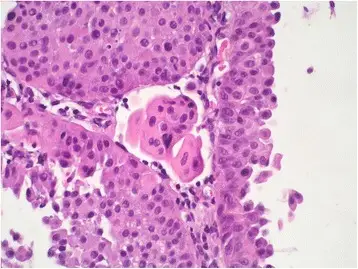

Urothelial carcinoma arises via two distinct pathways:

- Flat

- Papillary

Flat urothelial carcinoma is characterized by the invasion of a high-grade flat tumor and is associated with p53 early mutations.

Papillary urothelial carcinoma initially appears as a low-grade papillary tumor, advances to a high-grade papillary tumor, then invades, and is not linked to early p53 mutations.

A field defect is when a tumor recurs and is frequently multifocal in nature.